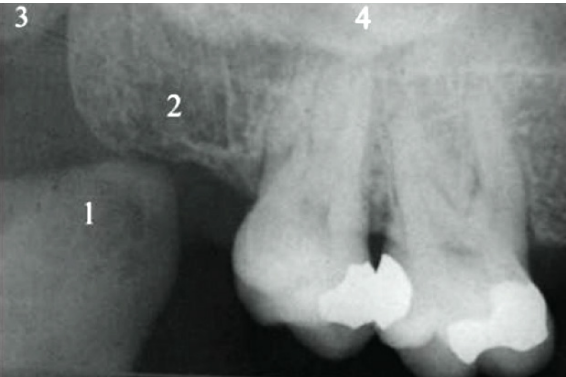

Observe a imagem abaixo de uma radiografia periapical de molares superiores:

Disponível em: Livro - Radiologia Odontológica e Imaginologia - Série Fundamentos de Odontologia 2ª ed.

Assinale a alternativa que corresponde à nomenclatura da estrutura anatômica marcada como 1 na imagem.